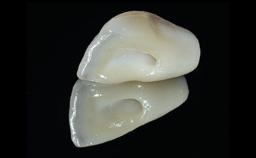

A 49-year-old female patient was referred for implant therapy to replace the upper right central incisor (tooth 11). The tooth had been assessed by an endodontist who diagnosed a vertical fracture of the root. The tooth had a hopeless prognosis and needed to be extracted. The patient was healthy and was not taking any medications. She was allergic to penicillin. The patient had high esthetic demands but her expectations were realistic. The extraoral examination revealed no facial asymmetries. The right temporomandibular joint demonstrated an opening click but was otherwise asymptomatic. The lip line was high with a significant gingival display.